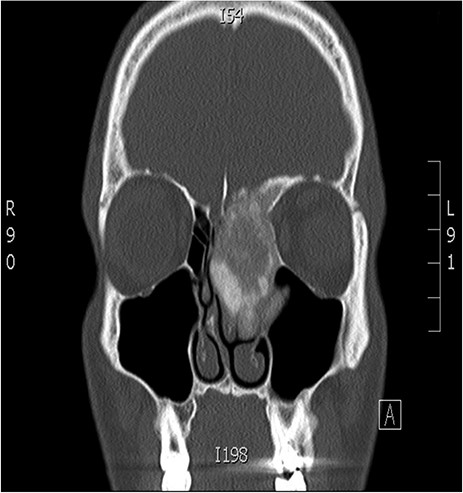

A 34-years-old man presented with left-sided facial pain, headache and nasal obstruction for a long duration, with no history of bleeding per nose, nor blurring of vision. Upon examination, there was a large left nasal cavity bony outgrowth pushing the middle turbinate and pushing the nasal septum to the right side (Fig. 1). CT scan of the paranasal sinuses showed a large mass centered in the left anterior ethmoid sinus, the mass measures 3.7 × 2.9 cm (trans-axial) (Fig. 2) and 3.7 × 5.2 cm (coronal) (Fig. 3), it has a heterogeneous density with calcified and soft-tissue component. The calcified component is in the periphery with central soft tissue density. The mass resulted in remodeling of adjacent bones with nasal septal deviation to the right, it extended superiorly to involve the frontal sinuses as well as invading the left cribriform plate and intracranial extension (Fig. 4), it extended inferiorly displacing the medial wall of the left maxillary antrum. The medial aspect of the mass caused remodeling of the medial wall of the left orbital cavity with bulging and displacement of the medial rectus muscle. The mass resulted in obstruction of the left frontal sinus.

Coronal CT image of the sinuses showing a large mass obstructing the frontal sinus.